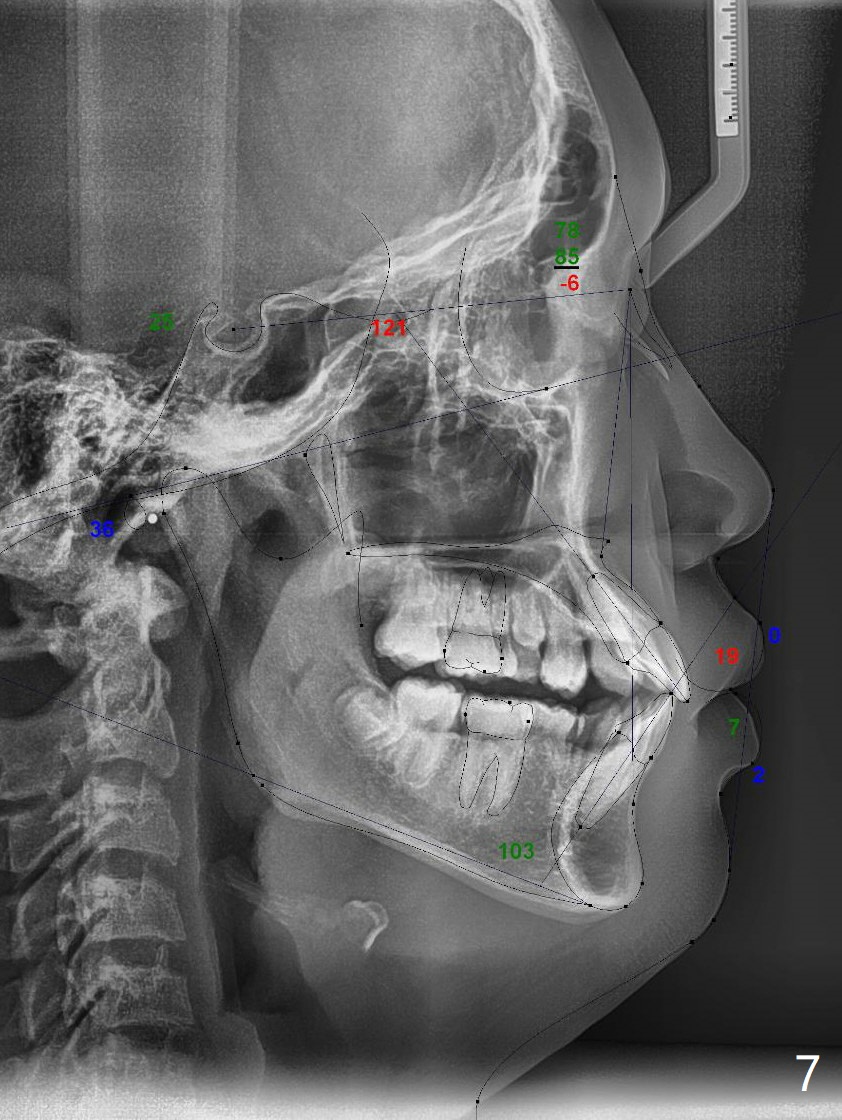

Pre-operative cephalometric X-ray shows convex facial profile (Fig.1). In fact tracing (a few days after banding) shows bimaxillary protrusion (SNA, SNB (88 and 87 degrees vs. 82, 80 (normal)). It appears that extraction orthodontics is indicated (UR4, UL5 (impacted) and LEs). The facial and upper dental midlines seem to coincide (Fig.2). No brackets or bands are placed at UR4 (because of non-cooperative (hyperactive)), LEs (Fig.3,4), or L7s (incomplete eruption, data not shown). Note wire bending between the canines and incisors, as related to correction of overbite. Shrinkable tubes are used in the region without bracket to prevent tissue injury. The upper arch seems to elongate (Fig.5, as compared to the lower one (Fig.6)). It appears that UR4 and UL5 should be extracted for normal profile and alignment. Cephalometric tracing shows that SNA and SNB are 79 and 85º, respectively, suggesting extraction (Fig.7).